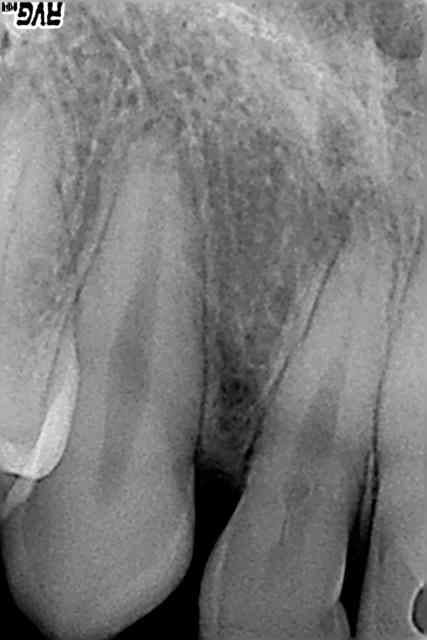

Un autre cas bizarre.

JH 19 ans

Pas d'antécédents de chute ni de traumatisme

Se plaint de douleurs constantes sur 12 depuis 1 semaine

Percussion +

Pas de mobilité

Test de morsure sur coton très douloureux

Test au froid négatif, positif sur la dent voisine

Jamais de soins sur la dent

Je note une inflammation gingivale avec un peu de plaque. Je lui fais une ordonnance avec AB et antalgiques. ça calme très rapidement les douleurs.

A l'arrêt des antibiotiques tout va bien.

Voici les radios R1,R2,R3 :

jour de la consult, 10j après, et 1 mois après.

Je remarque que la lumière canalaire est "perturbée" et je vois une zone radioclaire en évolution à l'apex, en distal, mais bon comment une dent saine comme ça peut se nécroser ?

Rachid_a_tort, il me semble voir sur la radio la projection d'une anomalie morphologique, une fissure d'un sillon palatin communiquant avec la pulpe, non ?

Oui ça me rappelle un cas récent d'une 12 avec un sillon très profond qui a induit une nécrose avec à la clé une "belle" cellulite qui a valu un passage à l'hopital à une jeune patiente... /-:

L'évolution rapide de l'image apicale donne envie d'intervenir de même rapidement pour faire le ttt endo en tout cas, nan?